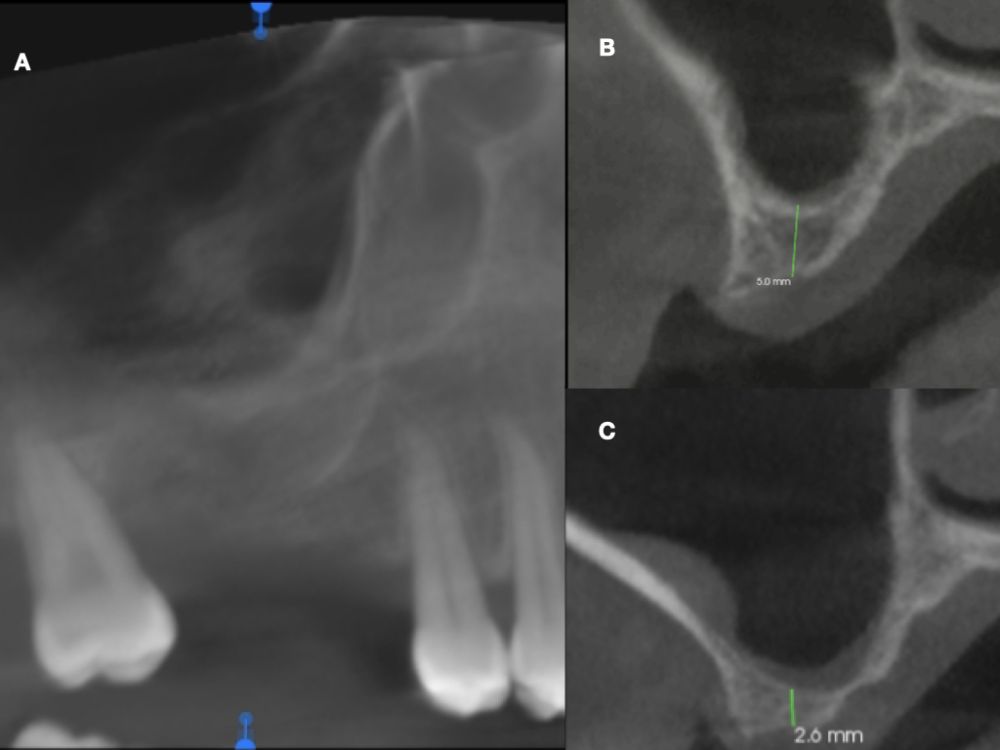

En la historia clínica, no se evidenciaron antecedentes médico-quirúrgicos de interés, alergias medicamentosas conocidas ni hábitos nocivos. A la exploración intraoral, se apreciaron las ausencias de 1.6 y 1.7 y la presencia del 1.8 y 4.8 (Figura 1). En la exploración radiográfica mediante escáner de haz cónico (CBCT) se apreció una altura residual de 5,0 mm en 1.6, donde se podría colocar un implante simultáneo, y de 2,6 mm en la zona del 1.7, dificultando la colocación de un implante de manera simultánea a la elevación de seno de acceso lateral (Figura 2).